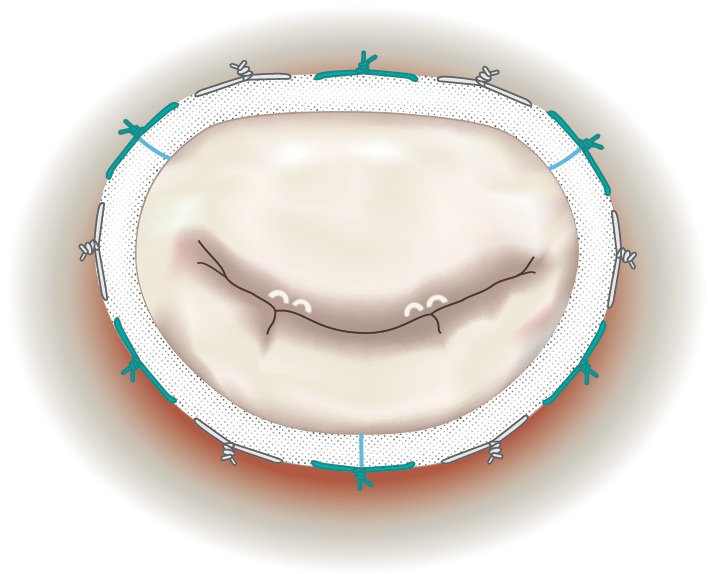

What Happens During Surgery to Repair the Mitral Valve?

During the operation, the valve is thoroughly inspected and a strategy developed for performing the repair. In the example below, several chords to the anterior leaflet are ruptured as well as leaflet prolapse and annulus dilatation.

|

| Chords to the Anterior Leaflet Ruptured with Leaflet Prolapse and Annulus Dilatation |

Artificial chords made out of GoreTex, which function like natural chords, are inserted at the location of the ruptured chords,. The sutures are then passed through the papillary muscles and are extended to the free edge of the leaflet.

|

| Artificial Goretex Chords Inserted and Sutures Passed through Papillary Muscles |

The suture length is then adjusted to conform to the geometry of the valve. Later, an annuloplasty ring is sized and implanted to support the repair, and maintain the optimized valve geometry.

|

| Annuloplasty Ring Implanted to Support Repair with Sutures Conformed to Value Geometry |